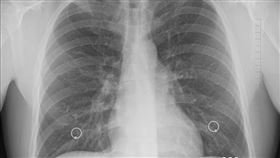

無基因突變肺癌治療 醫病溝通成關鍵

10:00